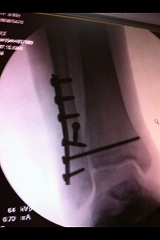

לפני חודש וחצי נותחתי ושמו לי פלטינות וברגים כילדהלמן:

זאת הרגל שלי מעכשיו:

http://rotter.name/User_files/nor/4fc695f605e01e06.jpg

http://rotter.name/User_files/nor/4fc695fb0605bf47.jpg

http://rotter.name/User_files/nor/4fc6960106125963.jpg